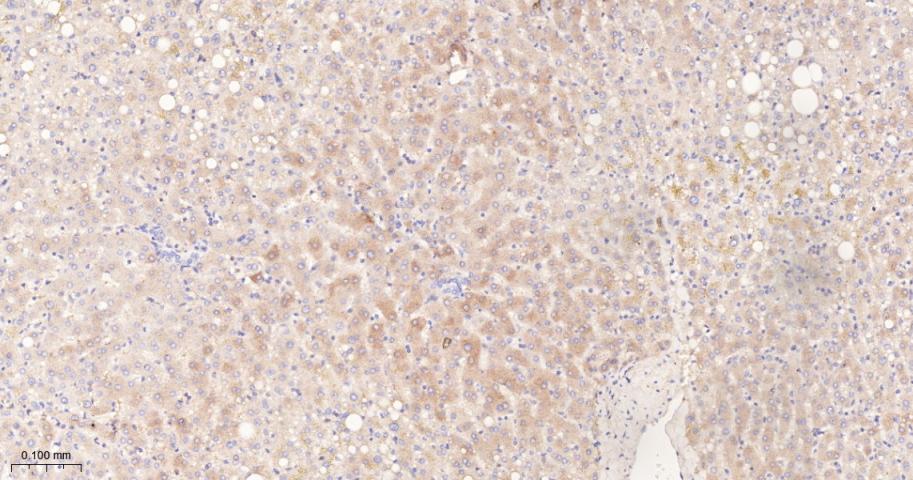

Paraformaldehyde-fixed, paraffin embedded Rat Liver; Antigen retrieval by boiling in sodium citrate buffer (pH6.0) for 15 min; The section was incubated with FDFT1 Monoclonal Antibody, Unconjugated (bsm-61816R) at 1:200 overnight at 4°C, followed by conjugation to the bs-0295G-HRP and DAB (C-0010) staining.